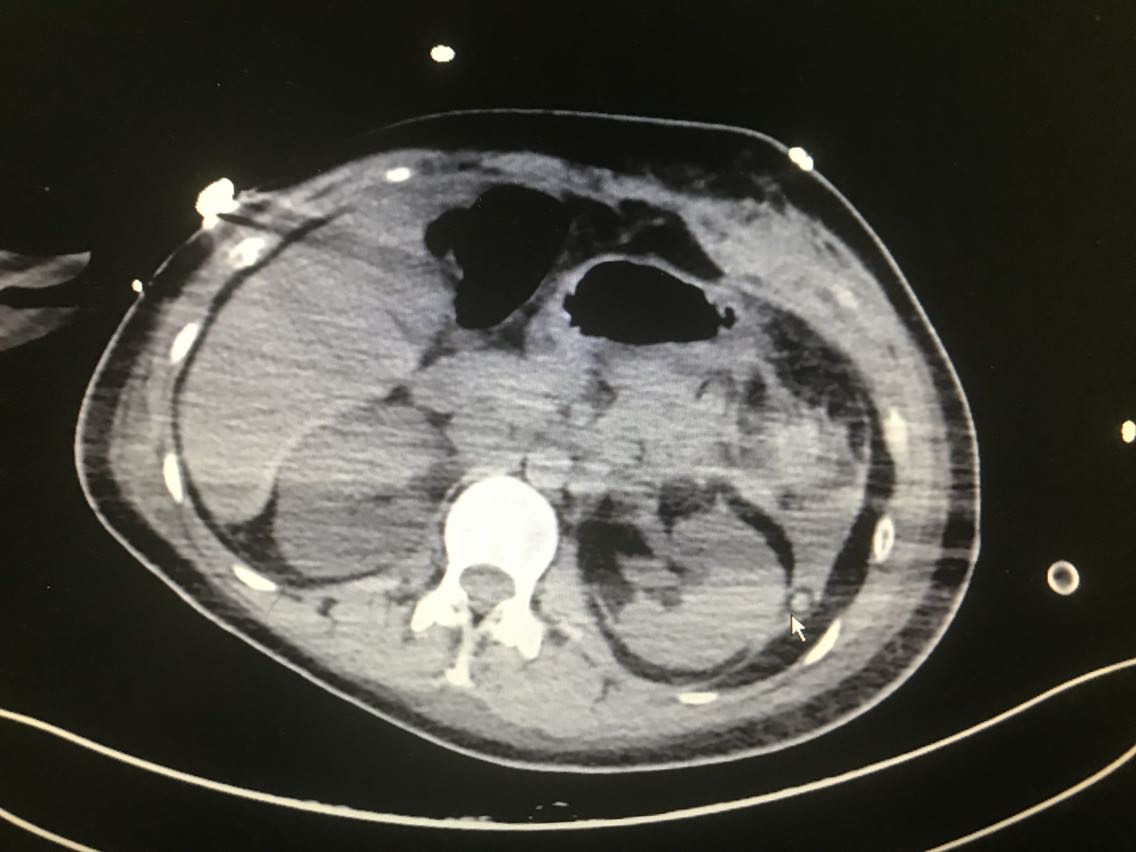

患者女性,31岁。 主诉:体检彩超发现左上腹异常回声10天 现病史:入院前10天,患者当地医院体检时彩超发现左上腹异常不均质稍低回声区,患者无胸闷胸痛、头晕黑朦、腹痛、乏力等不适,血压未见明显升高,近期体重未明显增加,二便正常,未予特殊处理。6天前患者于当地医院行增强CT检查示:左肾上极与胰脾之间肿瘤,疑为左侧肾上腺嗜铬细胞瘤,患者仍无胸闷胸痛、头晕黑朦、腹痛、乏力等不适。患者于我院就诊,诊断为左侧肾上腺肿瘤。患者目前为求进一步诊治,今日入住我科。 既往史无特殊。

查体:无特殊。 辅助检查: 腹部彩超示:左上腹见大小约10.8*7.0*6.9cm异常不均质稍低回声区,其内见大小约0.5*0.5cm强回声点。 全腹增强CT示:左肾上极与胰脾之间肿瘤:左侧肾上腺嗜铬细胞瘤?。

诊断:左侧肾上腺肿瘤。 治疗:腹腔镜左肾上腺肿瘤切除术+肠粘连松解术+左肾周粘连松解术 术中见:左肾上腺肿瘤约8x8x7cm肿瘤,肿瘤滋养血管增生紊乱,左肾上腺肿瘤与左肾上极及周围组织粘连,左肾周粘连。